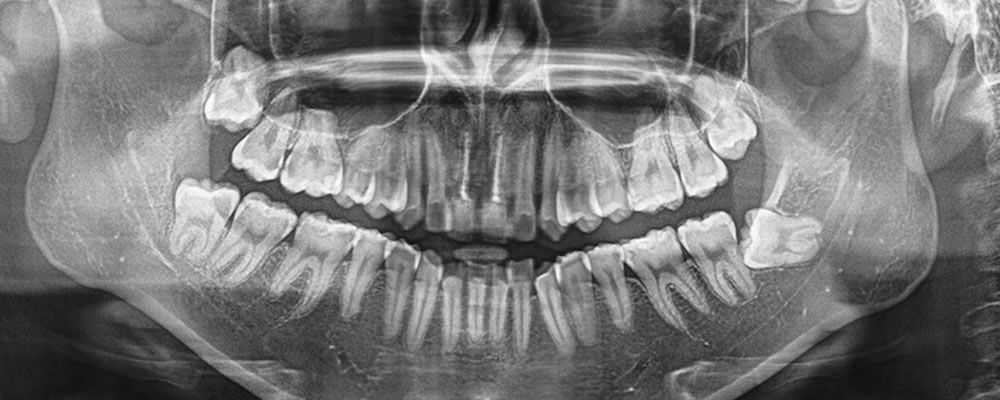

こちらの患者さまは、歯根破折により他院から両側中切歯のインプラント治療を依頼され、当院を受診されました。

抜歯即時埋入およびPRPを併用した骨造成を行いました。ISQ値(インプラント安定指数)が十分でなかったため、即時荷重(インプラント体を埋入直後、または短期間で仮歯などを装着し、噛む力(咬合力)を加える方法)は行わず、手術を終了しました。

顎骨とインプラントがしっかりと結合したことを確認後、完成した上部構造(人工歯)を装着して治療完了となりました。

治療前後の比較